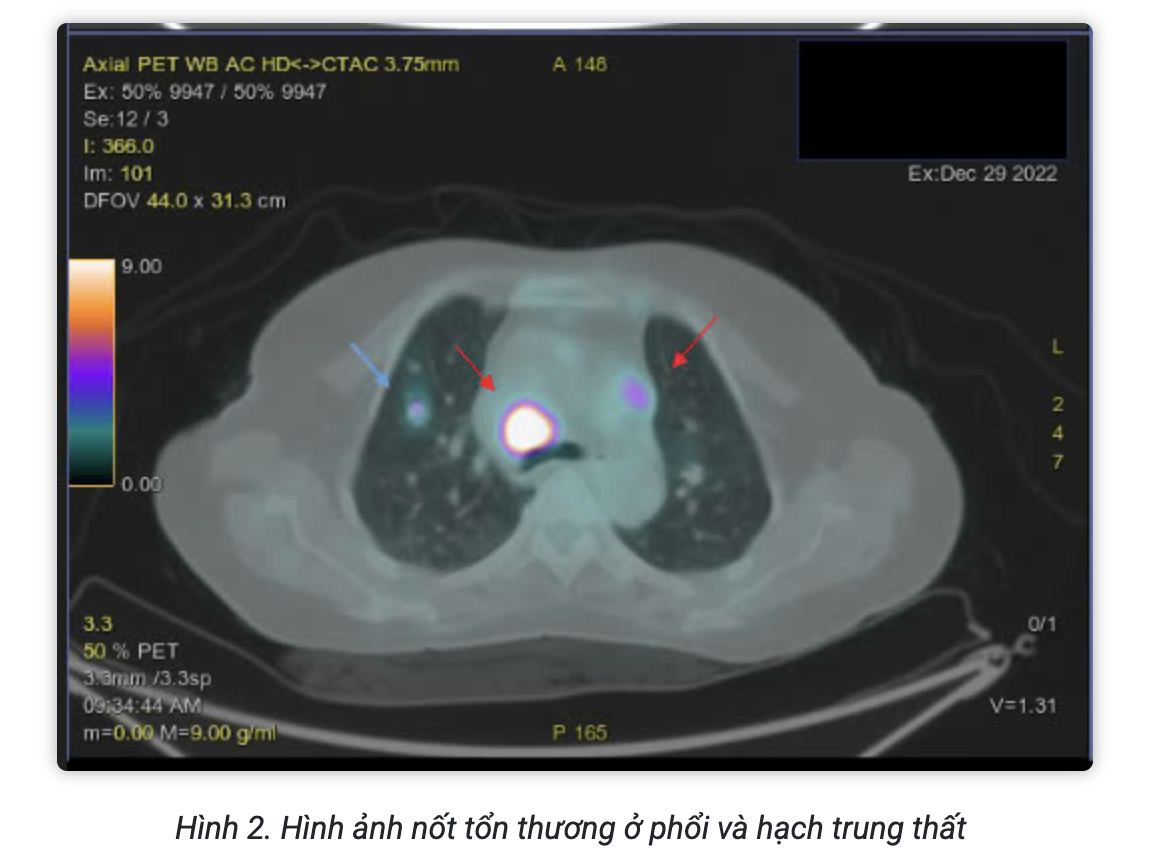

Hình ảnh PET/CT với F18-FDG đánh giá giai đoạn trước điều trị:

Kết luận:

- Hình ảnh hạch cổ 2 bên, hạch trung thất, hạch ổ bụng, hạch bẹn 2 bên tăng chuyển hóa FDG hướng tới ác tính.

- Hình ảnh nốt tổn thương phổi phải, tổn thương xương bướm, tăng chuyển hóa FDG hướng tới ác tính.